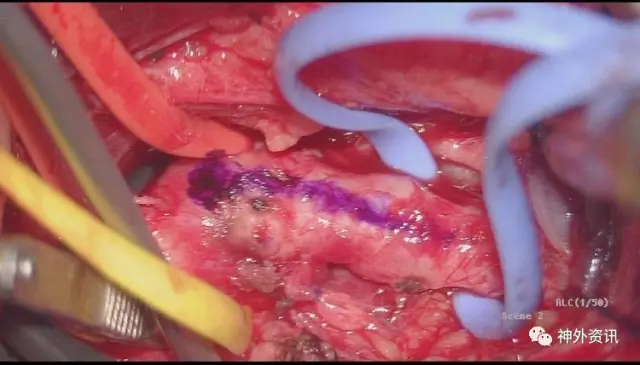

在肌肉下方我们发现了横向外下的胸导管,黄箭头所示

充分游离、显露ⅤA起始段,锁骨下动脉向内外显露各约1.5cm,于血管下留置橡皮条,以方便术中阻断

标记VA内置支架段内膜剥离直切口,阻断锁骨下动脉远近端,马上可以切除支架了